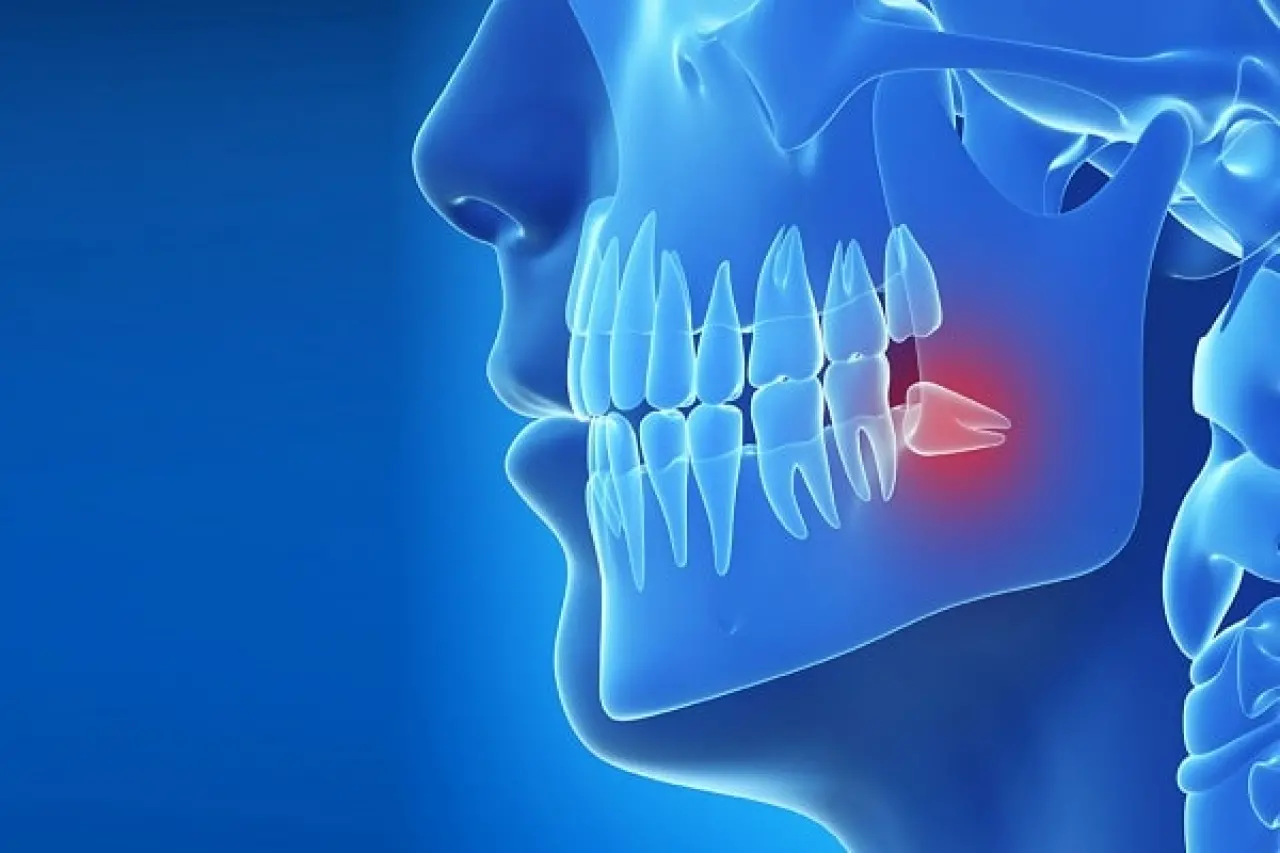

Tamamen gömülü olabilir (çene kemiği ve diş etinin altında kalır).

Kısmen gömülü olabilir (dişin bir kısmı çıkar, bir kısmı diş etinde kalır).

Yan yatmış şekilde çıkabilir (komşu dişe baskı yapar).